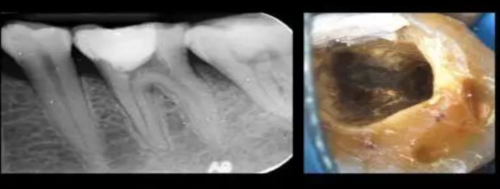

6)制作桩核冠桩核(树脂核)。

2、牙体预备:去净腐质和变色牙本质,尽量保留健康的牙体组织,必要时制备洞斜面;

3、护髓和垫底:根据窝洞深度及临床症状选择适宜的牙髓保护方法,深大窝洞可行流体树脂垫底、玻璃离子垫底或结合护髓剂进行修复。